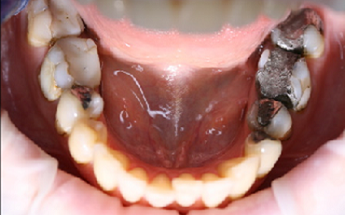

Foto 9-13: Fotodokumentace situace v ústech - vlevo, vpravo, uprostřed, v horní a dolní čelisti.